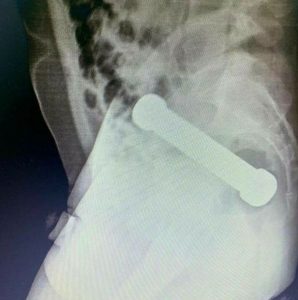

When medics at the hospital in Manaus, Brazil, were unable to remove the object using tweezers, they opted for a “manual extraction”.

This meant they put their hand into the man’s bum to remove the dumbbell.

According to a report in the International Journal of Surgery Case Reports written by Dr Ana Elisa de Landa Moraes Teixeira Grossi and her team, a surgeon inserted their hand “up to the forearm” to get a grip on the item.

Dr Ana wrote: “Despite the location of the object being considered high, manual transanal extraction was chosen, inserting the surgeon’s forearm with some difficulty, without post-extraction complications.”